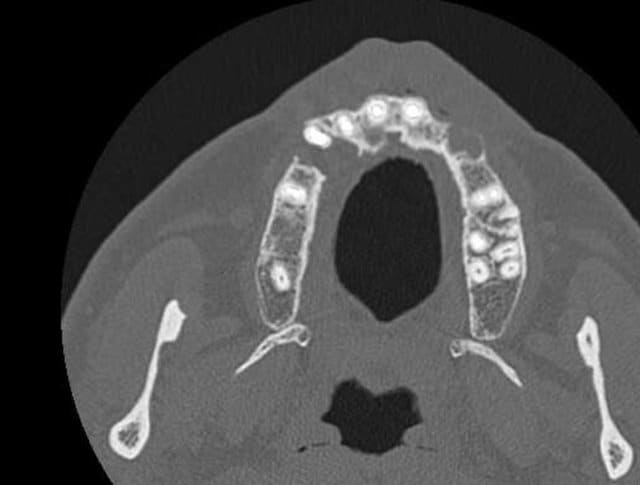

Voilà j'ai mieux que la gutta (pas de fistule visible en ce moment de toute façon )

Un scan. Voici quelques extraits.

Donc on extrait tout ce qui reste devant, on est d'accord ?

il semble y avoir une communication avec les sinus frontaux visible sur les coupes ,personnellement je serai très méfiant sur les extractions,que je déléguerais car les suites risques de ne pas être si simples, et ne les ferais pas sans avoir préalablement défini un plan de traitement post chirurgical surtout si le patient ne se plaint de rien actuellement;car ce type de situation mal anticipée peut amener des conflits.

J'ai pas prévu de réaliser cette chirurgie moi même heureusement. Le radiologue a en effet parlé au patient d'un possible commnunication (mais rien sur le compte rendu officiel bien sur).Si il y communication, celà posera t-il problème pour réaliser un comblement en vue d'un traitement implantaire ?